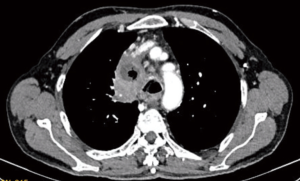

Presence of features of locally advanced disease (Figure 2) makes decision easier but this is not the case always. VATS should be seen only as a minimally invasive tool for mediastinal tumors resection and the limitations of this approach should not be considered as its disadvantages. Most of its disadvantages like high infrastructure costs and limitation of tactile sensation were similar to any other minimally invasive procedure. However, in infants and smaller children paediatric VATS demands very small calibre instruments which may not be easily available. Due to lower incidence of cases and technical and structural problems there is a slower progress in achieving experience in VATS even among purely paediatric centres (78). This leads to scarcity of adequate training facilities when compared with adults.